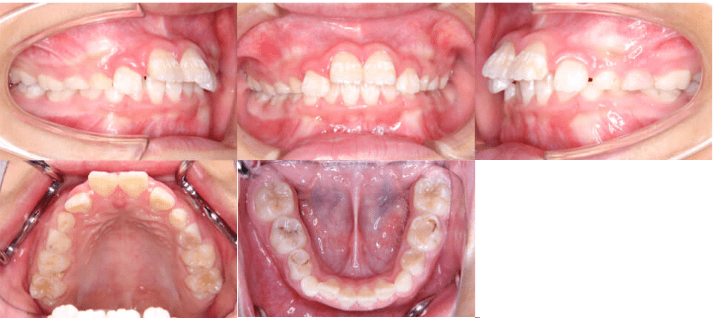

治療前

治療後

• 初診時年齢:8歳5ヶ月

• 主訴:上の前歯がでていて口が閉じづらい

• 診断:過大なオーバージェットを伴う過蓋咬合症例

• 治療内容:マウスピース型カスタムメイド矯正歯科装置(製品名インビザライン 完成物薬機法対象外)使用して主訴である上の前歯の突出を改善しつつ、前歯のかみ合わせが深い過蓋咬合についても下の前歯を押し下げて上あごの歯ぐきを噛まなくなるように改善しました。

• 治療期間:10ヶ月

• リスク:矯正治療による歯の移動に伴う痛み、歯根吸収、虫歯

• 費用:40万円